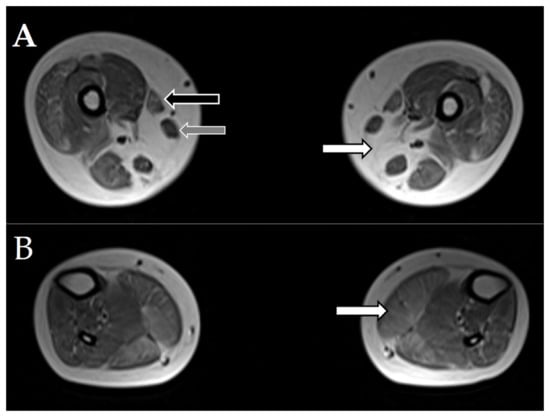

| Muscle MRI: severe symmetric changes in the iliopsoas, semitendinosus, and tibialis anterior muscles and slightly less pronounced abnormalities in the sartorius, gracilis, adductor magnus, short head of the biceps femoris, vastus, and gluteus muscles. | |||||||||

| Muscle MRI: absence of the semimembranosus muscle, severe fatty infiltration in the cervical and thoracic paraspinal, serratus anterior, and gluteus maximus muscles, moderate changes in the adductor magnus, sartorius, vastus lateralis, and gastrocnemius muscles and sternocleidomastoid muscle atrophy | |||||||||

| 8a | recessive SELENON | M | 3 mths | floppy baby syndrome, motor development delay, dysphagia | Moderate weakness: proximal > distal, upper < lower rigid spine, dysmorphic myopathic face, high arched palate, wadding gait | Not on heels | 114 | Myopathic | Chronic respiratory failure after pneumonia at age 4 noninvasive ventilation (BiPAP) required during the night. |

| Muscle MRI: absence of the semimembranosus muscle, severe fatty infiltration in the cervical paraspinal, serratus anterior, gluteus maximus, and sartorius muscles, moderate changes in the thoracic paraspinal, latissimus dorsi, pectoralis major, rotator cuff, adductor magnus, vastus lateralis, biceps femoris, semitendinosus, and gastrocnemius muscles and SCM atrophy | |||||||||